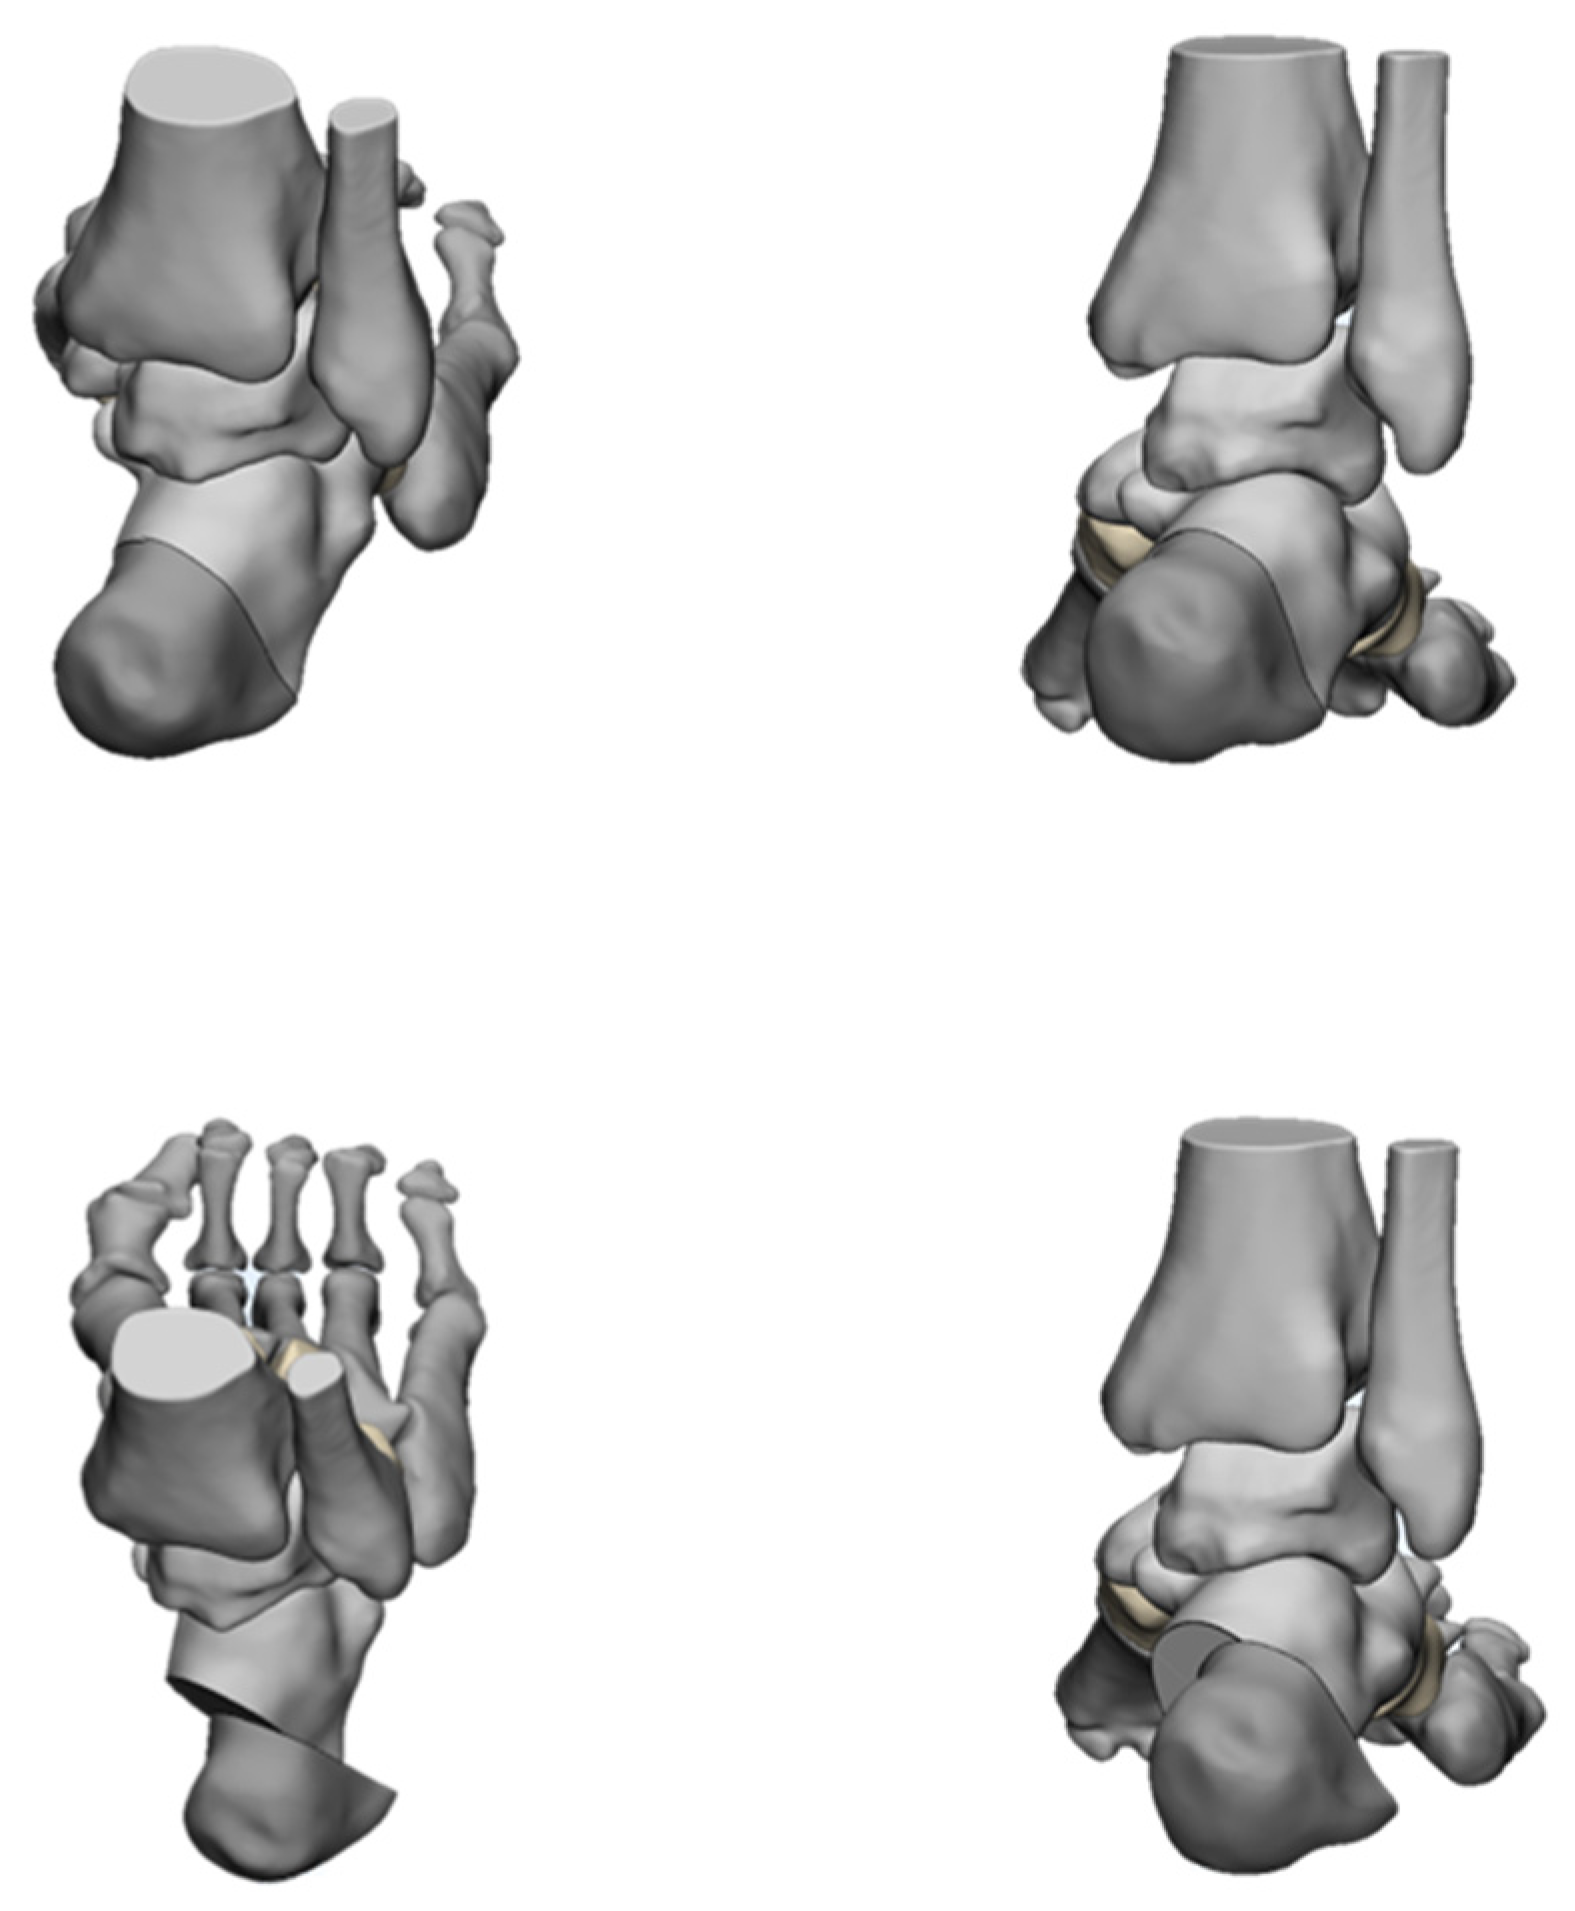

The deformities involved in cavus foot are complex and include the abnormal elevation of the medial arch, varus hindfoot, high calcaneal pitch, high-pitched midfoot, plantarflexed, claw toe, and adducted forefoot. The anatomical structure of the cavus foot can be better understood by building a three-dimensional model. (Figure 2). The front view of this model shows the rotation and varus of the forefoot. From the AP (anterior–posterior) view of the model, the adduction and supination of the forefoot will be seen. The TC (talo-calcaneal) angle becomes narrow. From the lateral view, the first ray is in a dramatic plantarflexion position and the fifth ray is overloaded. Viewed from back to front, the varus and pronation of the hindfoot are apparent. Such structural changes seriously affect the flexion and extension of the midfoot by affecting the “lock” and “unlock” mechanism of the Chopart joint, resulting in excessive load on the lateral side of the foot in the varus position. During the gait cycle, the foot remains locked in the forefoot and hindfoot varus position throughout the stance phase, resulting in less stress desorption. These structural changes may lead to metatarsal pain, fifth metatarsal stress fracture, plantar fasciitis, medial longitudinal arch pain, and even iliotibial band syndrome [7].

Figure 2.

Three-dimensional view of cavus foot.